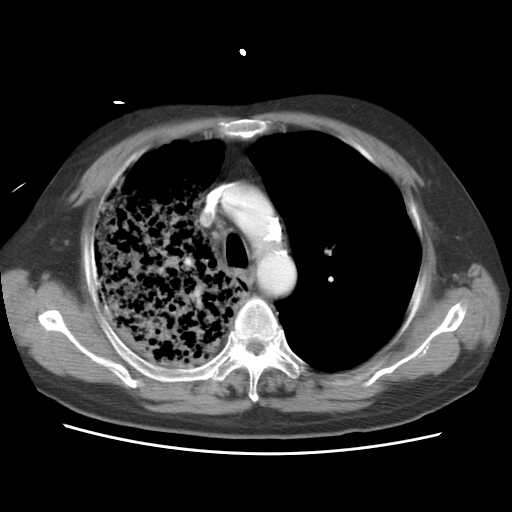

2008.8.17ct

病变从8.11-8.17明显改变,增多,以蜂窝状改变为主,类蜂窝肺,似弥漫性肺泡癌,但是病变进展太快,不符合弥漫性细支气管肺泡癌。因此考虑为特殊微生物感染,多以霉菌类常见,建议细菌微生物学检查。

疑点二:影象表现怪异,大片阴影内见多发筛孔征,如何解释.

间质为主,血管炎性水肿?

结合临床慢支炎肺气肿,肺心病病史,三次胸片观察可见病情发展变化迅速,病情凶险,考虑多重感染伴ards.